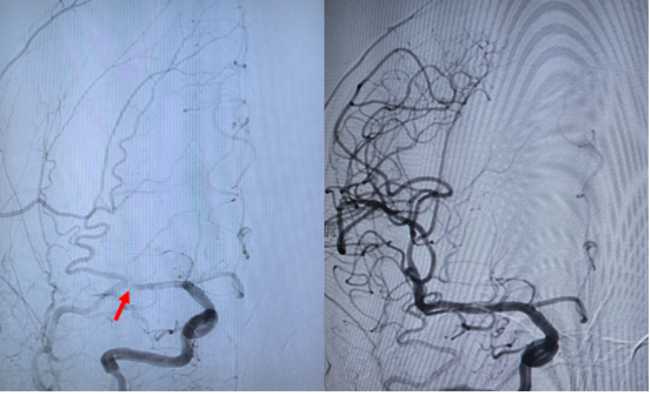

闫鹏、李懋禹医生与家属充分沟通并获得知情同意后,患者被紧急送入导管室。麻醉、穿刺、建立通路,术中视野显示血栓负荷远超预期——右侧颈内动脉系统从主干到分支,广泛分布着松散血栓。闫鹏沉着冷静、步步为营,凭借精湛的操作技术,很快成功开通了堵塞的血管。在反复观察确认血流持续稳定通畅后,直至凌晨4点,他才放心走下手术台。患者随后转入神经重症监护室继续治疗。

动脉开通前后对比